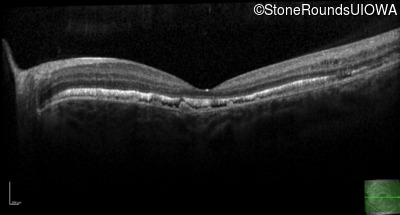

Optical Coherence Tomography - Left - 20/25 -3 sc

Exemplar / OCT Stack

OCT Stack